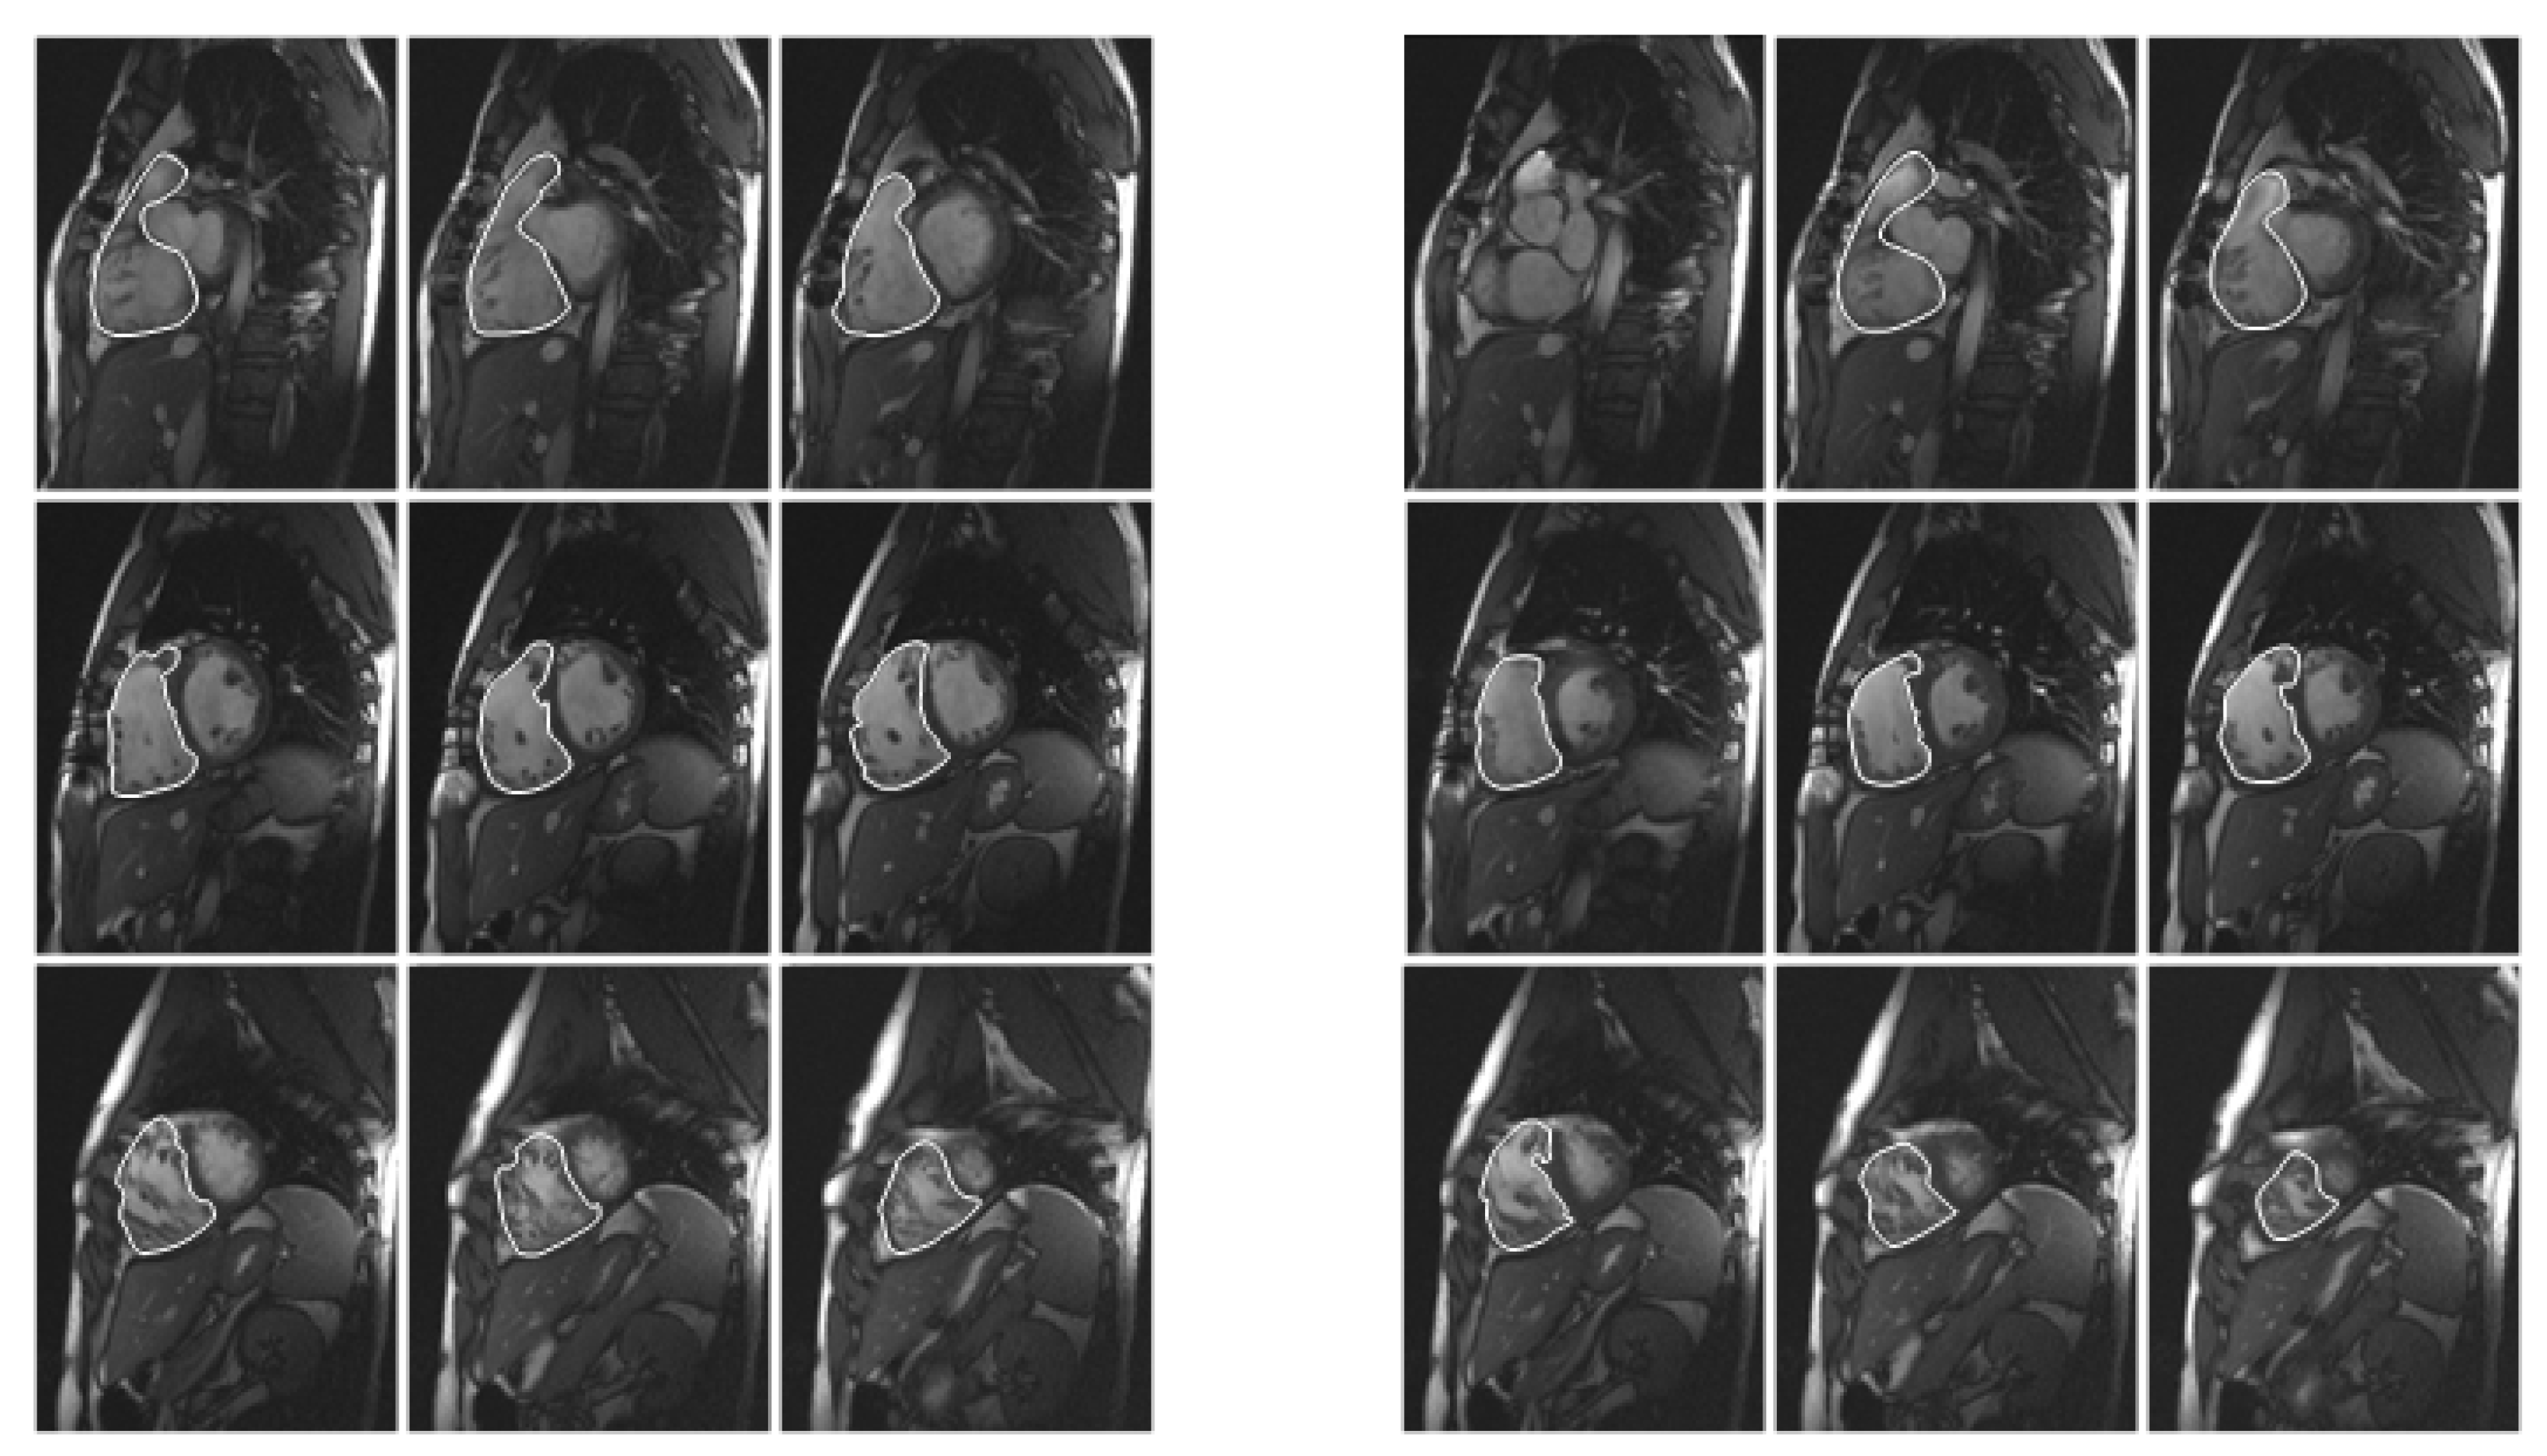

2.3. Image Analysis

2.4. Manual Method

2.5. Semiautomatic Method